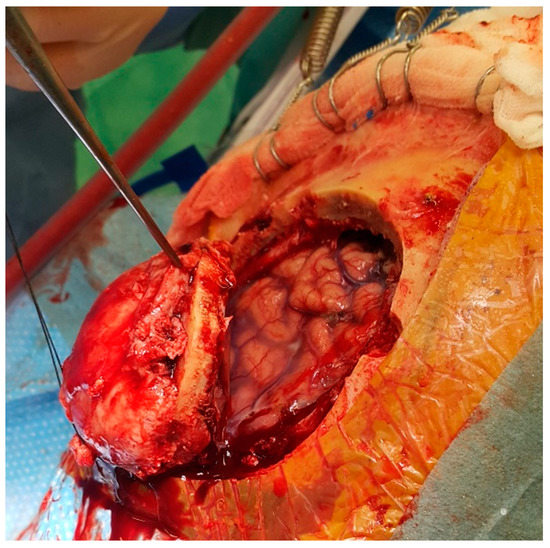

It has been reported that cranioplasty with autologous bone grafts is associated with high overall complication rates in comparison to bone substitutes. Among them, PEEK and poly-methyl-methacrylate have relatively low complication rates. One of the important disadvantages is an infection, which may occur with autologous bone and bone substitutes as well. In such cases, the removal of the autologous or artificial flap is needed to heal the infection properly (Figure 7). Unusually, these infections are not life-threatening and may be quickly resolved with antibiotic therapy; however, the recovery course is prolonged, and in the later phase, another cranial reconstruction is needed [84,85,86,87].

Figure 7. The original bone flap has been infected and partially resorbed, as documented on CT with 3D reconstruction. The craniofixes can be seen, fixing the bone flap to the skull. This infected bone flap will be surgically removed and replaced by a new one made of poly-methyl-methacrylate, that was manufactured in vivo.